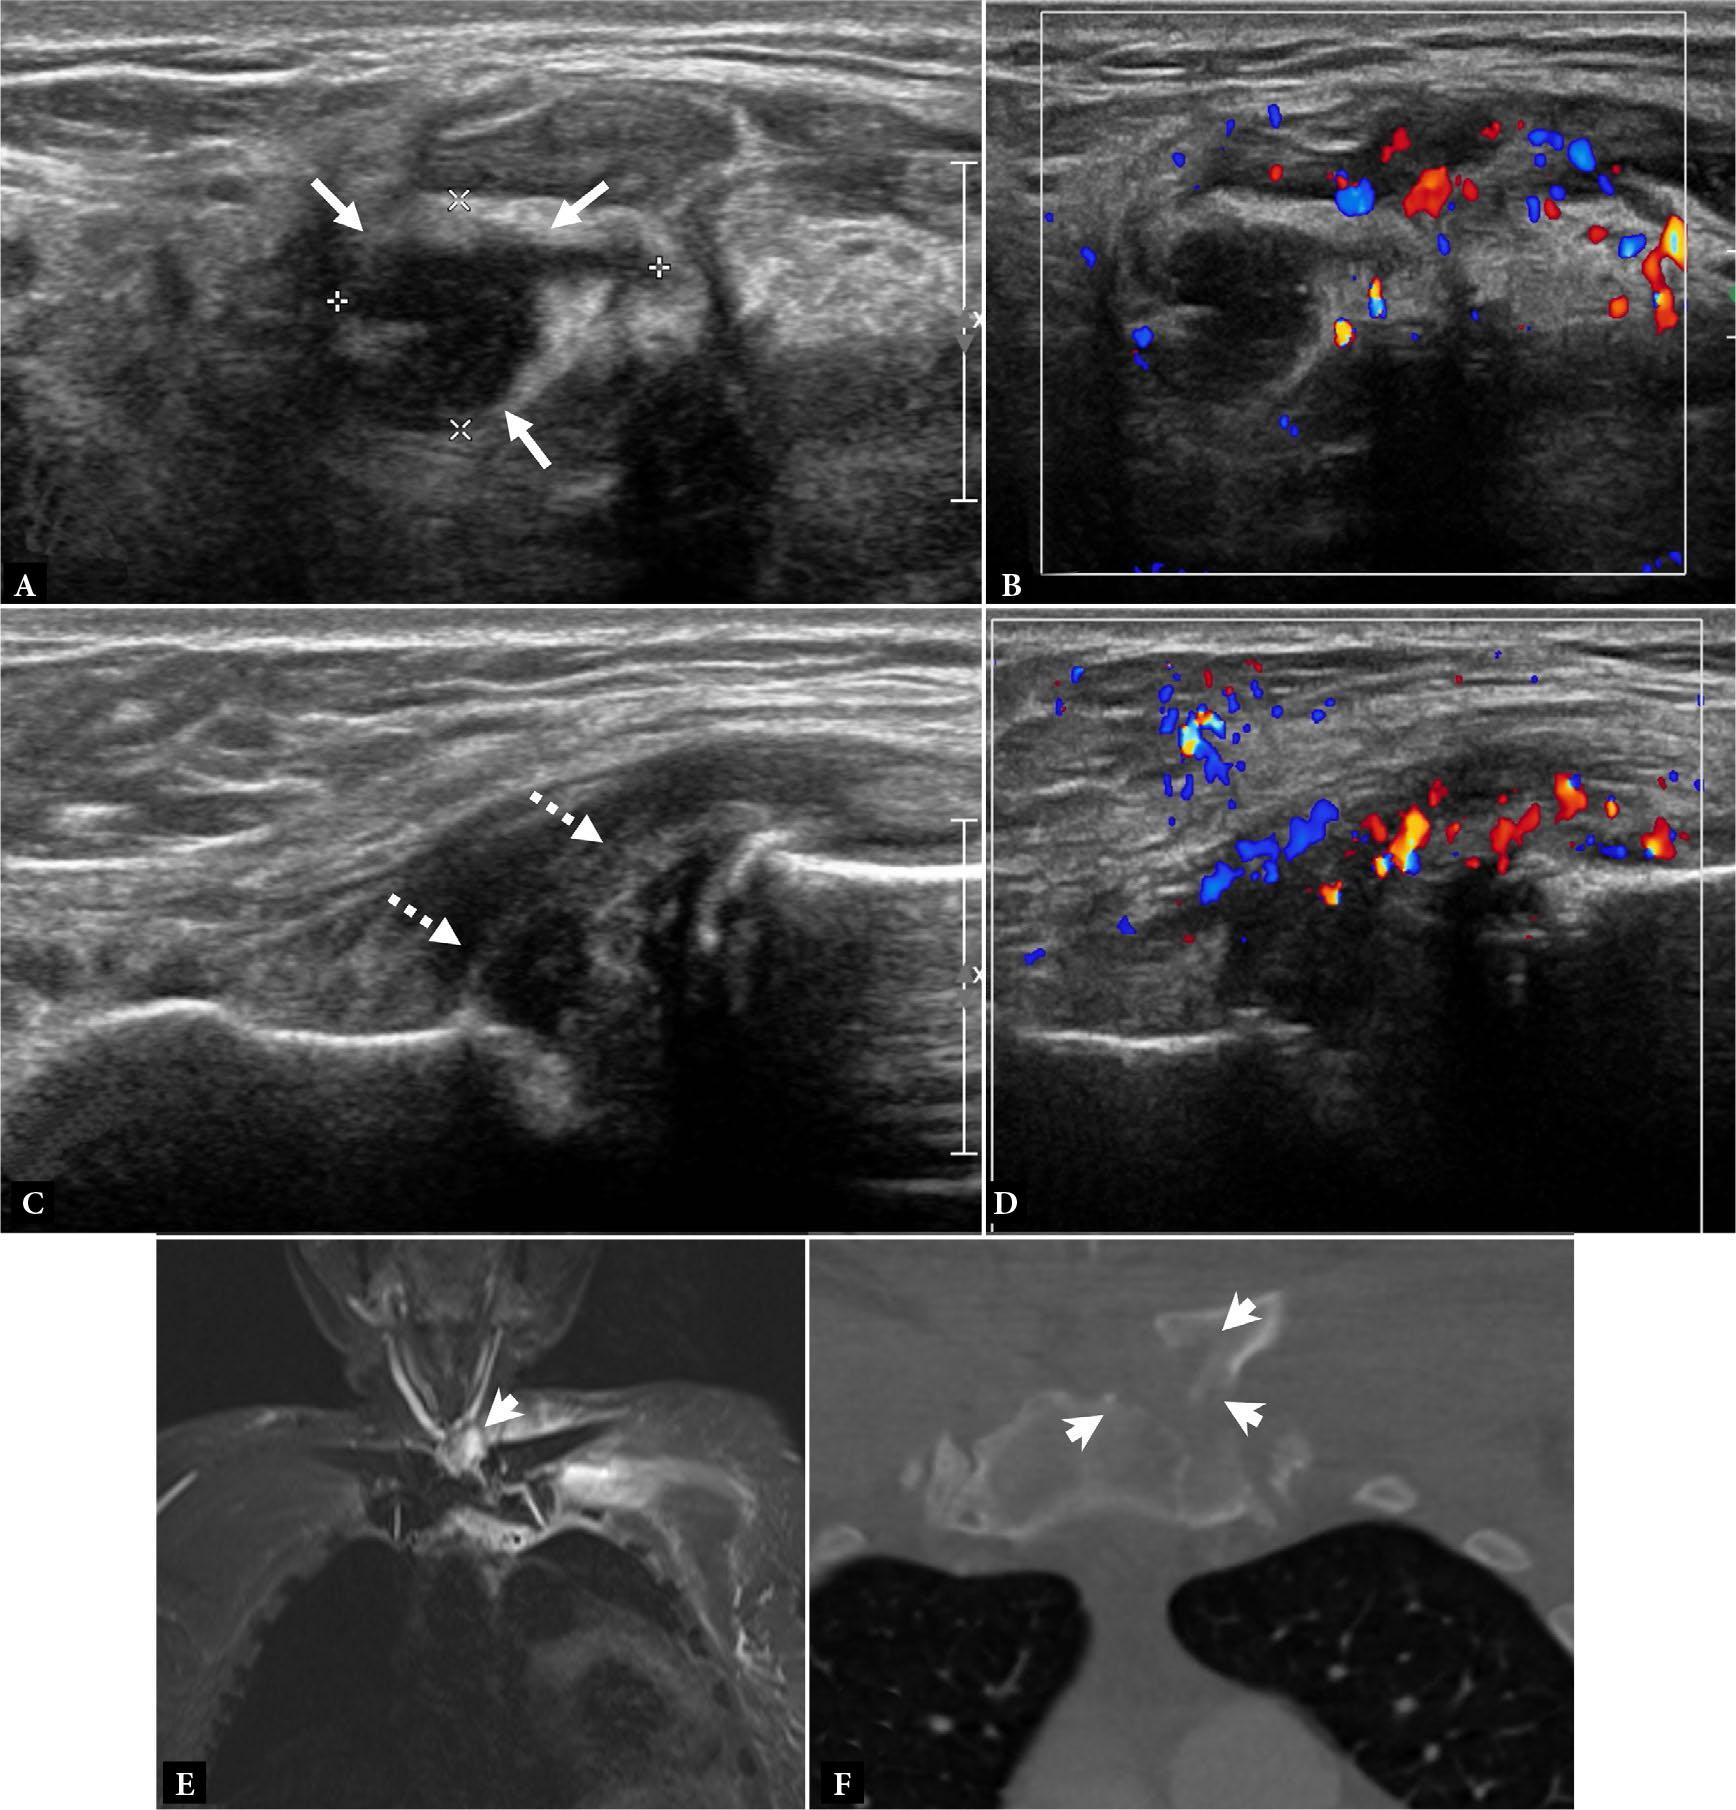

Fig. 3.